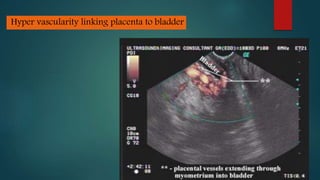

Ultrasound and MRI are used to diagnose placenta accreta, which occurs when the placenta invades the uterine wall due to prior uterine surgery or other risk factors. On ultrasound, signs include low placental implantation, lakes or indentations in the placenta, thinning of the myometrium, disruption of the uterine serosa, and abnormal blood flow on Doppler. MRI may show uterine bulging, a heterogeneous placenta, thinning and interruptions of the myometrium, obliteration of tissue planes, and dark bands within the placenta. These imaging findings help identify placenta accreta and guide management of delivery.